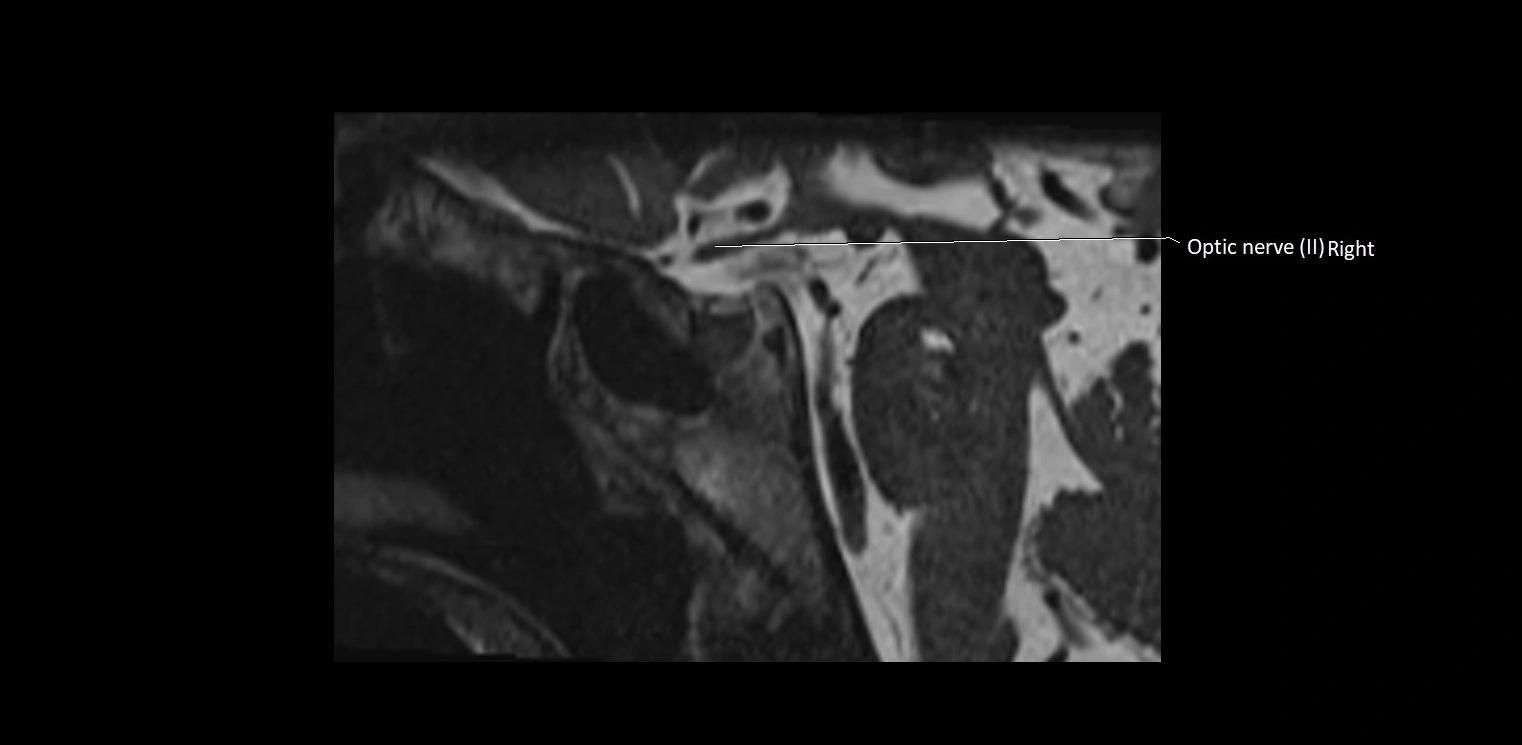

MRI Appearance

• The abducens nerve is a small, thin, linear structure

• Best visualized on high-resolution T2-weighted 3D MRI sequences (e.g., FIESTA or CISS)

• Seen as a hypointense (dark) line running from the brainstem at the pontomedullary junction, traversing the prepontine cistern, and entering Dorello’s canal under the petrosphenoidal ligament, then into the cavernous sinus, and finally the orbit

• May be challenging to visualize in standard MRI due to its small size

• Pathology may be inferred by absence, displacement, or enhancement of the nerve